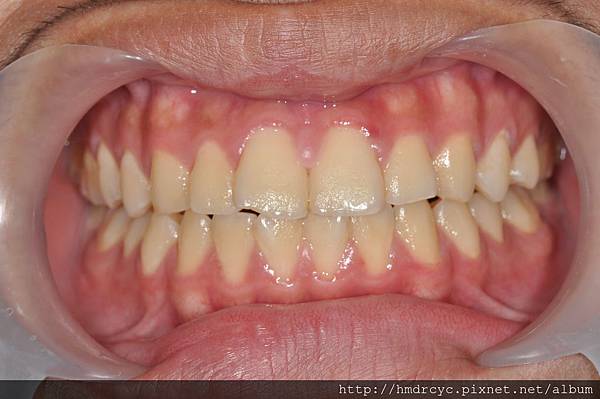

台北念書的Z小姐有相同問題

單純牙肉發炎沒有骨頭吸收

經過洗牙治療,三天後牙肉消腫回到原本位置